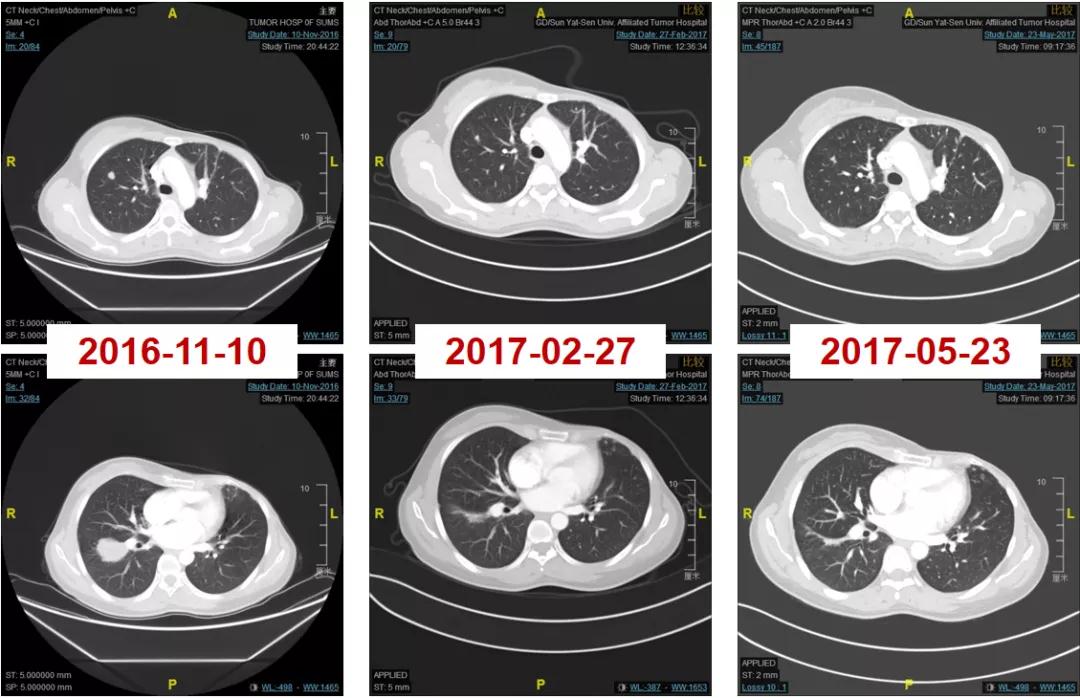

2016-06-01复查CT:右肺下叶上段团块状肿物(图1),考虑转移。

图1